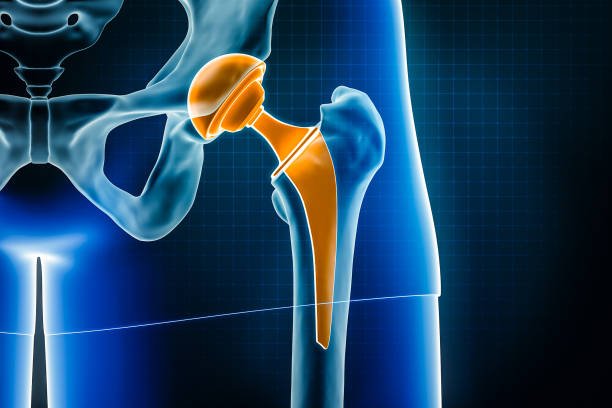

2. Total Hip Replacement (THR):

For patients experiencing debilitating hip pain due to arthritis, fractures, or other conditions, our Total Hip Replacement services offer a reliable solution. Our surgeons utilize minimally invasive techniques to reduce recovery time and improve surgical outcomes, ensuring that patients can return to their daily activities with greater ease.